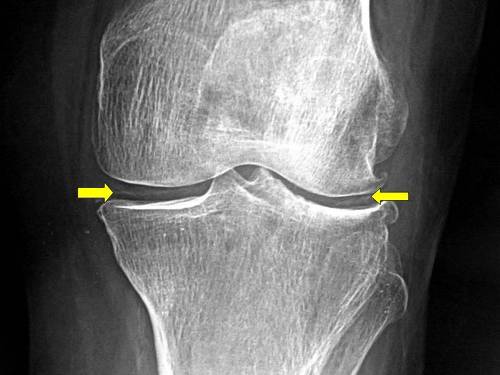

- Множественная кальцификация суставного хряща на рентгенограмме.

Все эти признаки характерны только для данной патологии и помогают поставить правильный диагноз даже без клинических проявлений. Однако зачастую приходится проводить дифференциальную диагностику с подагрой, острым септическим артритом и деформирующим артрозом.